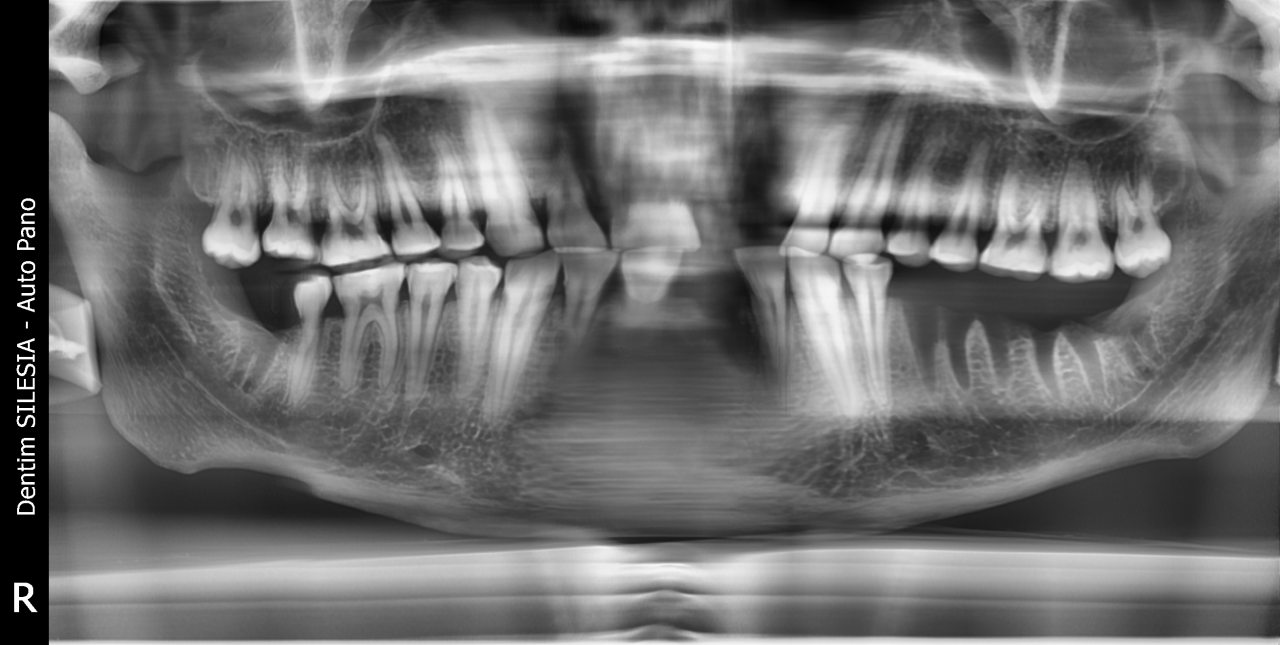

– Na przegląd stomatologiczny z Muzeum w Gliwicach zostało przekazanych 6 czaszek lub ich części, z czego 5 należało do osób dorosłych, a jedna do młodego dorosłego. Wykonaliśmy podstawowy przegląd, badanie pod kątem próchnicy (DiagnoCam), wybrane zęby były oceniane pod mikroskopem, pobrano również skany 3D i przeprowadzono cyfrową diagnostykę radiologiczną. Każdy z „pacjentów” miał założoną typową kartotekę, w której zaznaczano spostrzeżenia dentystów. Całość trwała 3 intensywne dni, a po tym czasie eksponaty wróciły do Muzeum – opisuje przebieg badań lek. dent. Marta Szymańska-Pawelec, dentystka odpowiedzialna za projekt z Dentim Clinic Medicover w Katowicach.

– Na podstawie diagnostyki radiologicznej można wnioskować, że wskutek nieleczonej próchnicy u jednego z pacjentów powstała zmiana torbielowata przy korzeniu zęba trzonowego. Osoba ta nie mogła widocznie liczyć na żadną pomoc chociażby cyrulika, więc pozostawiony, zainfekowany korzeń spowodował destrukcję ograniczeń kostnych i przewlekły stan zapalny błony śluzowej zatoki szczękowej – opisuje dentysta.

– Nawet najbiedniejsi, którym nie dokuczały choroby czy wady rozwojowe, jak się okazuje, wcale nie musieli wiele robić. Tylko w nielicznych przypadkach wykryliśmy próchnicę, co stanowiło około 20-30% zębów, a dzisiaj na nią uskarża się niemal 9 na 10 osób! Nie ma w tym nic dziwnego, jeśli spojrzymy na dietę. Wieki temu spożywano nieprzetworzone lub niskoprzetworzone produkty: zboża, kasze, pieczywo, wędzone mięsa, warzywa i owoce. Rafinowany cukier przez wieki był towarem luksusowym i bardzo drogim. Częściej do słodzenia był stosowany miód. Nie bez znaczenia mogła być też obecność fluoru w wodzie, który występuje w niej naturalnie. Kiedyś nie była filtrowana, jak obecnie – mówi lek. dent. Szymańska-Pawelec.

I, jak dodaje dentystka, warte odnotowania jest ponadnormatywne starcie zębów: – Zęby niektórych osób były bardzo starte, aż widoczne były odsłonięta zębina i miazga. Wynikać to może z charakteru spożywanych produktów, które były twarde, włókniste, a w chlebie mogły znajdować się okruchy kamienia z młyna. Obecnie starcie zębów przypisujemy stresowi, który wyzwala często nieświadome zgrzytanie zębami. Czy wtedy tak bardzo też się stresowano? Pewnie tak, choć powody były zupełnie inne.

– W jednym przypadku zaobserwowaliśmy cechy przewlekłego zapalenia przyzębia, co skutkowało zanikiem kości części zębodołowej żuchwy z tzw. obnażeniem furkacji korzeni. To znaczy, w uproszczeniu, że tkanki były tak nisko aż dostrzegalne były nawet korzenie zębów trzonowych. Z tego powodu osoba ta, za życia, mogła już wcześniej utracić zęby, bo miejsca po brakach były zagojone – opisuje chirurg z Dentim Clinic Medicover.